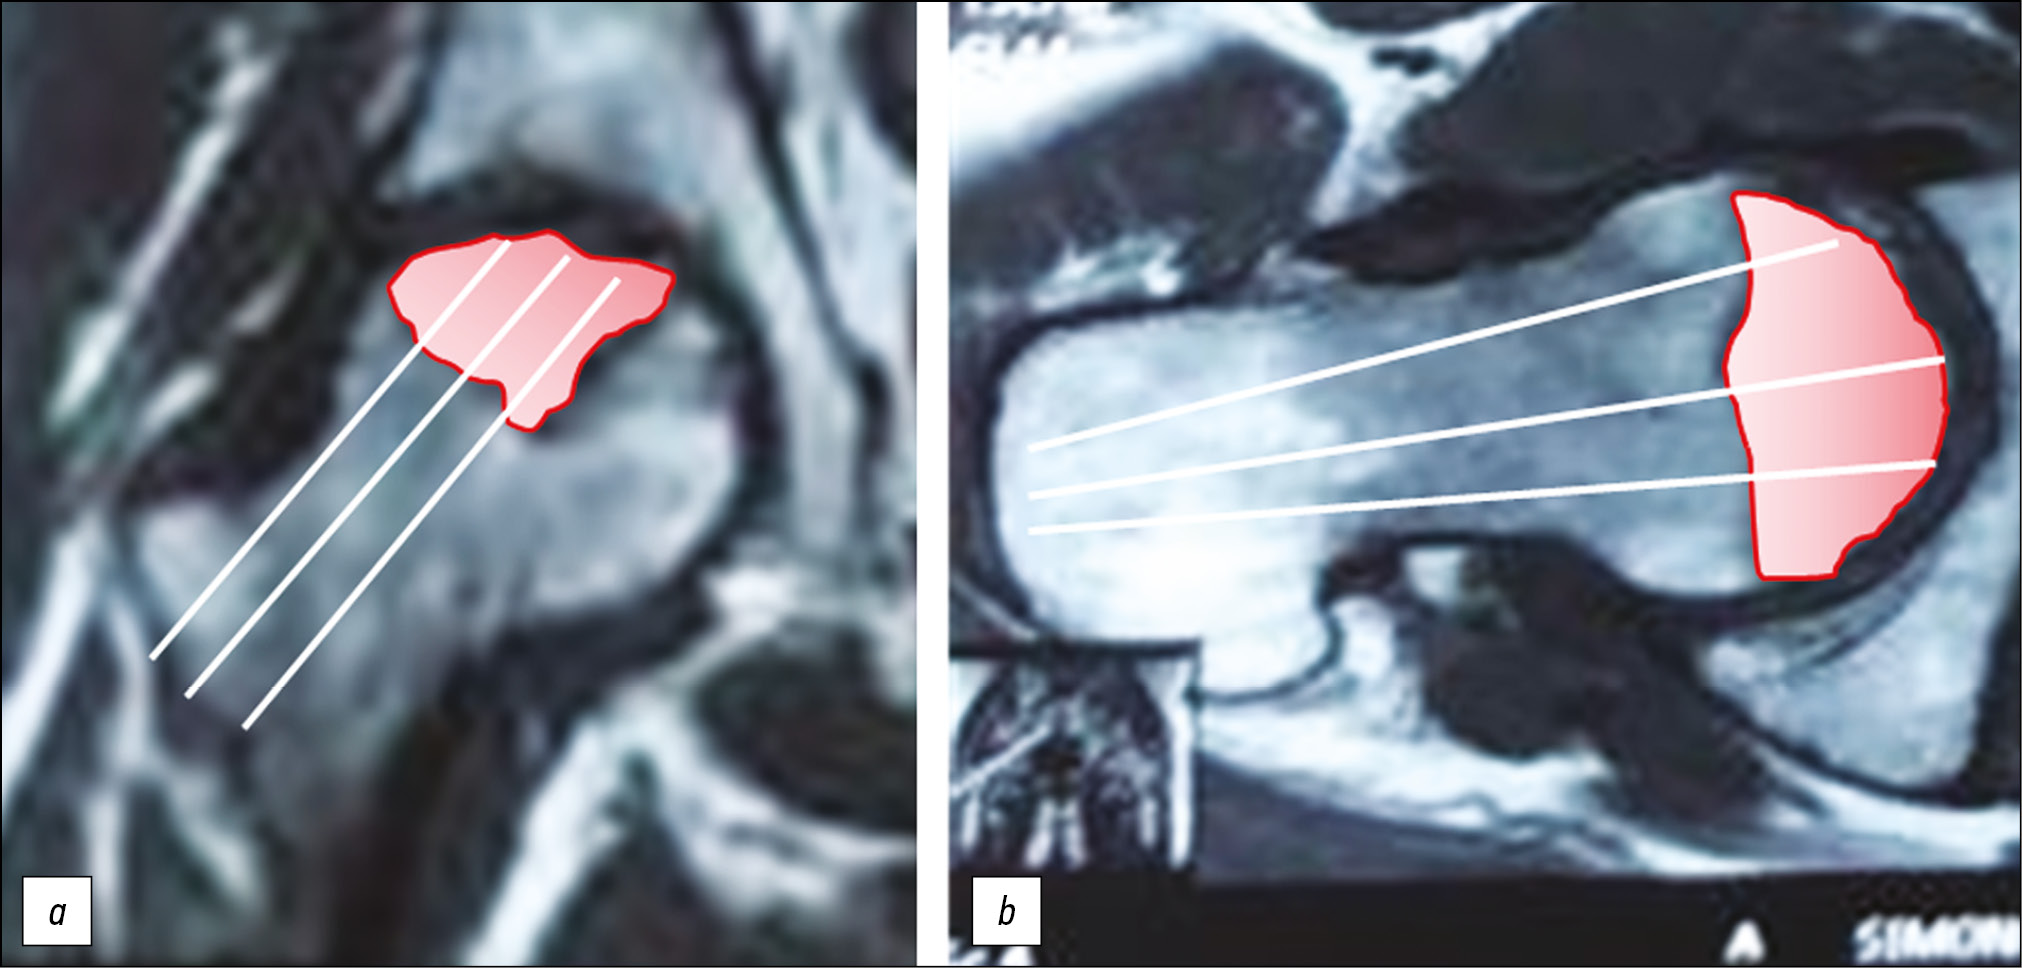

В группу 2 (группа сравнения) вошли 25 пациентов, оперативное вмешательство которым ограничилось классической декомпрессией очага некроза. У пациентов данной группы количество направлений каналов для декомпрессии и их число (от 3 до 5) определялись на этапе предоперационного планирования и зависели от размера и локализации очага некроза по данным магнитно-резонансной томографии (МРТ) (рис. 2).

Рис. 2. Предоперационное планирование декомпрессии очага некроза у пациента II группы. a — фронтальная проекция; b — аксиальная проекция.